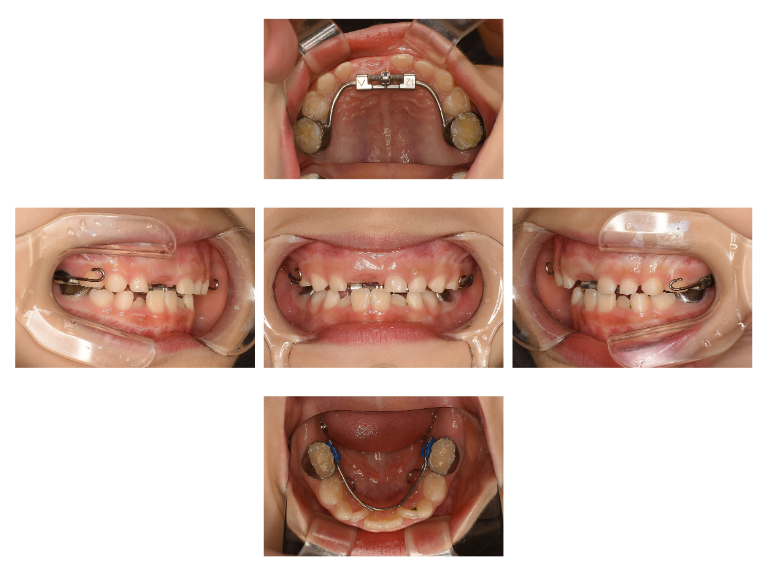

術中

| 治療名 | 小児矯正 |

|---|---|

| 治療説明 | 将来の歯並びが悪くなる可能性が非常に高いと判断されたため、上顎に急速拡大装置、下顎にリンガルアーチを用いて小児期の矯正治療を行いました。大人の歯が映えるスペースを確保し、上下の顎のアンバランスも改善できました。 |

| 治療回数・期間 | 1年 |

| 副作用とリスク | 大人の歯の位置や方向を完全にコントロールできない可能性があり、追加の成人矯正が必要になる可能性があります。治療期間が長くなる可能性、複数回の装置作成が必要となる可能性があります。 |

| 料金(税込) | 550,000円 |